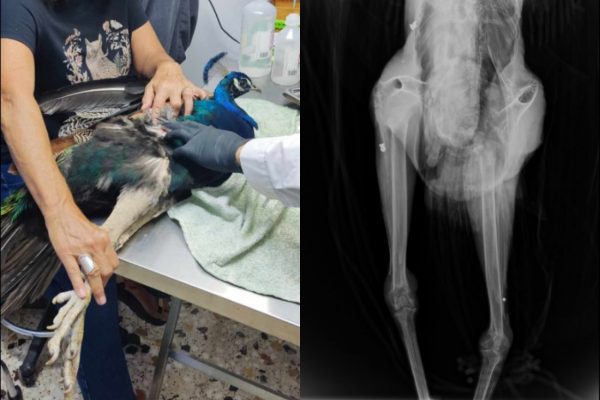

«Το παγώνι έχει πυροβοληθεί τρεις φορές, προς έκπληξή μας στην ακτινογραφία είδαμε δυο βολίδες αεροβόλου κι ένα σκάγι» αναφέρεται σε ανάρτηση του συλλόγου ΑΝΙΜΑ